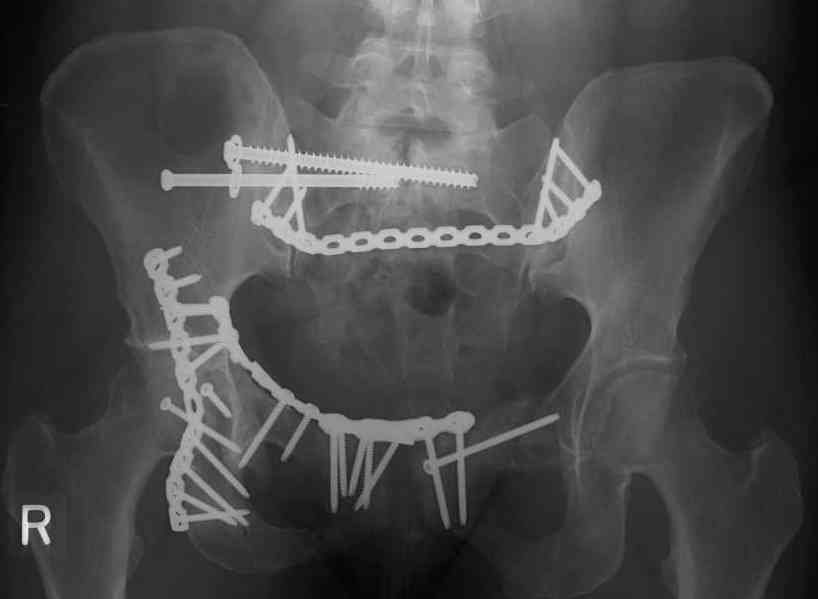

Looking for advice. This is a 48 yo non-smoking female s/p MCC 10 months ago. I do not have the initial injury films. She underwent ORIF as shown on attached file. She is having continued pain in low back/sacral region. Worse with sitting and prolonged walking. Has had pain since surgery. All of her wounds have healed uneventfully. Also has right hip pain laterally. No groin pain. Not aggravated with ROM of the hip. Infection work-up has been negative.

Any thoughts on the broken plate on the pelvic brim and the non-union on the anterior column. Doesn't seem like she's have pain from there.

Suggestions on treatment of sacral nonunion.